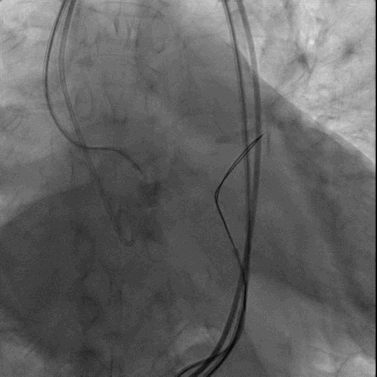

经右股静脉置入7F JR指引导管至下腔静脉,经右股动脉置入6F猪尾导管至腹主动脉,于下腔静脉及腹主动脉同时造影精确定位目标穿刺点。

穿刺系统与圈套器配合完成穿刺并建立下腔静脉至腹主动脉的通路

后续TAVR步骤与常规经股动脉TAVR类似:依次行主动脉根部造影、导丝跨主动脉瓣并交换猪尾导管、经左股静脉置入临时起搏电极、主动脉瓣球囊预扩张、在快速起搏下植入经导管主动脉瓣。

主动脉根部造影